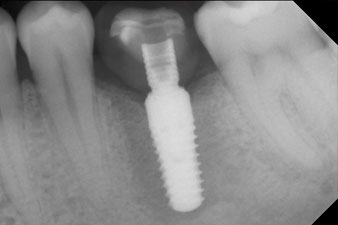

The final pictures show the screw-retained monolithic composite crown in place and the x-ray check (Fig. 9 and 10) (6).

The implant stability is better described as micromobility and is best measured by resonance-frequency analysis (RFA) (7, 8). Measurements are best made in two directions, as in the case study (9). The technology is optionally available as a module that can be docked to the Implantmed implantology motor. A separate device is not required. The lower value is always applicable for the therapy. Measured values are displayed on the touch screen of the implantology motor as the implant-stability quotient (ISQ). Along with the torque curve for insertion and data on preparation of the implant bed, they can be recorded on a USB stick and used for documentation for the patient and the implant. Overall, it is a very user-friendly and reliable technology for everyday work in implantology, particularly in combination with the W&H Implantmed.